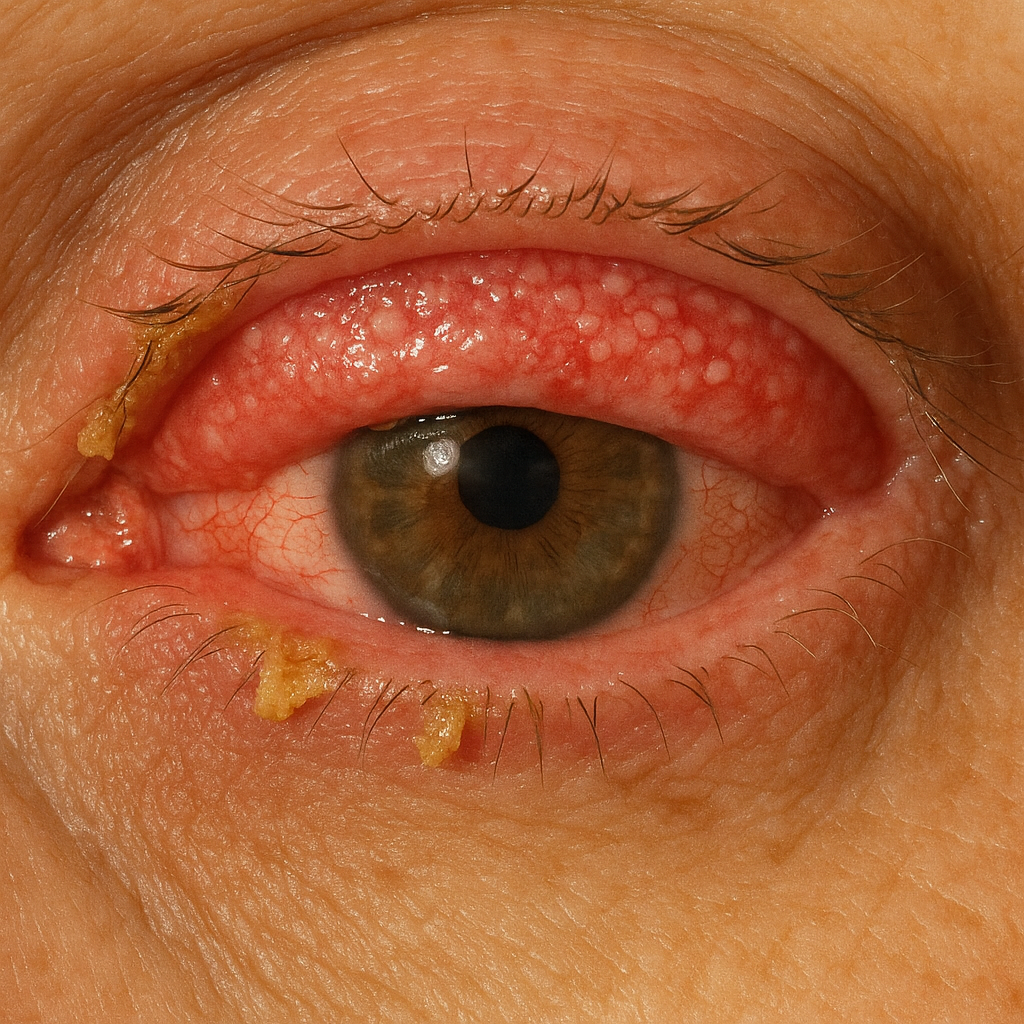

# Eyes